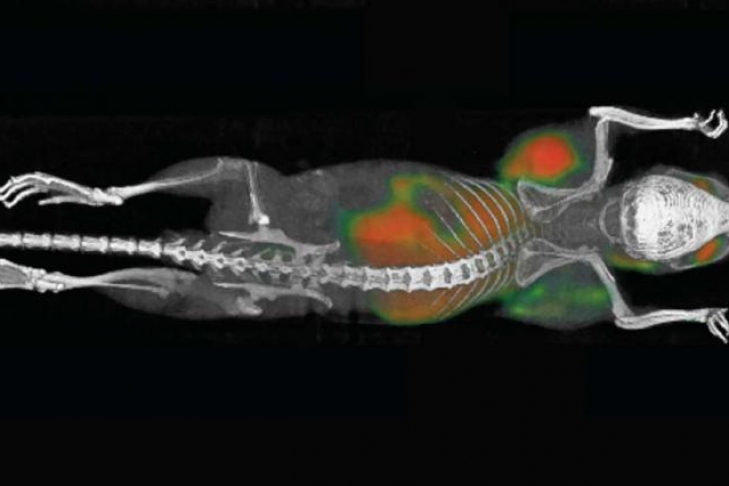

В испытаниях использовали 90 мышей, в организм которых искусственно ввели клетки лимфомы. У каждой мыши образовалось по две опухоли — у правого и левого плеча. Животные получили инъекции в одну из опухолей. После инъекции опухоли начали уменьшаться, для 87 животных из 90 лечение прошло успешно с первой попытки. При этом уменьшалась не только опухоль, в которую сделали инъекцию, но и вторая, незатронутая. Трем оставшимся мышам терапия помогла со второй попытки. Дальнейшие опыты показали, что метод работает для мышей с меланомой и опухолями молочной железы и толстой кишки.